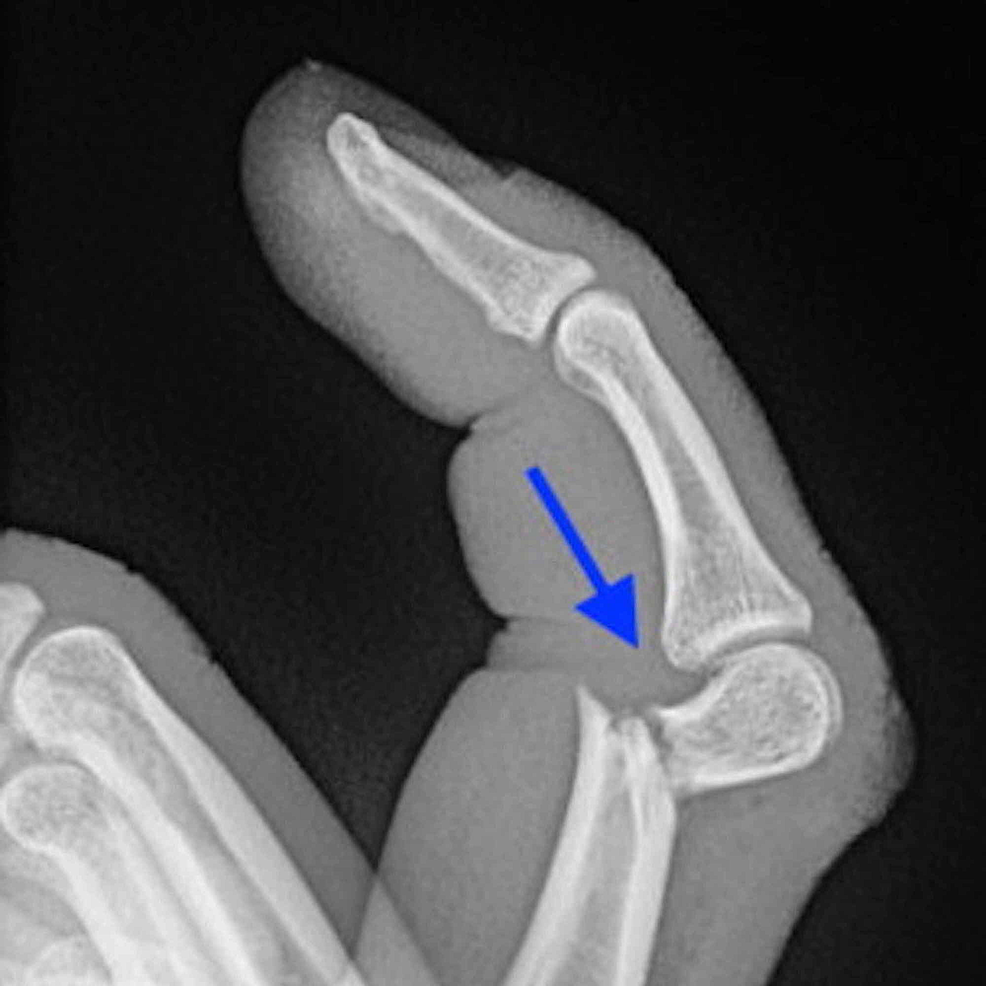

손가락 뼈에 금이 가면 깁스 치료는 필요한가

많은 분들이 가장 궁금해하는 부분이 바로 “손가락 뼈에 금이 갔을 때도 깁스를 해야 하는가”입니다. 결론부터 정리하면, 모든 경우에 깁스가 필요한 것은 아닙니다. 손가락에 발생하는 미세 골절이나 비전위성 골절은 스플린트만으로도 충분한 안정성을 확보할 수 있는 경우가 많습니다.

반대로 깁스 또는 보다 강한 고정이 필요한 경우는 다음과 같습니다.

- 골절로 인해 뼈가 어긋난 경우

- 관절면이 손상된 경우

- 여러 조각으로 부러진 분쇄 골절

- 스플린트 착용 후에도 통증과 불안정성이 지속되는 경우

즉, 손가락 뼈에 금이 갔다는 진단만으로 깁스를 결정하기보다는, 골절의 형태와 안정성, 기능 손상 여부를 종합적으로 고려해야 합니다. 과도한 고정은 오히려 관절 강직을 유발할 수 있으므로, 최소한의 고정으로 최대의 회복을 목표로 하는 것이 치료의 핵심입니다.